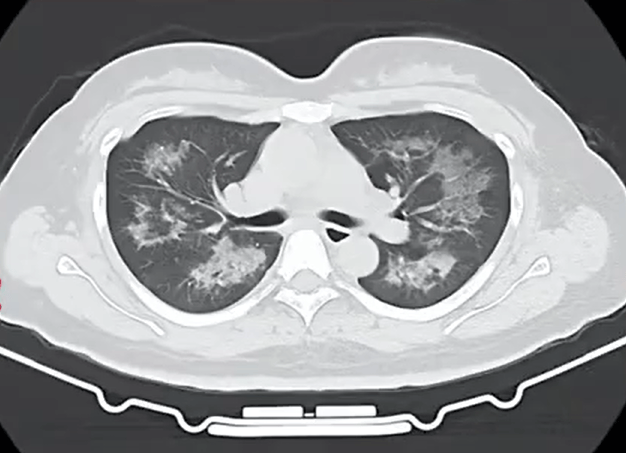

胸部CT进一步显示,她的双肺出现多发斑片状模糊影,被诊断为间质性肺炎丹阳有哪些证券公司。医生判断,病因很可能与她近期长期接触的某类物质相关。经过医生反复细致地询问病史,小江才说出自己存在长期、频繁使用定妆喷雾的情况。